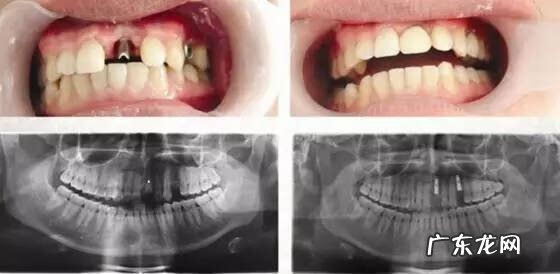

50多岁的陈先生是女儿陪同其来的,“几年前,父亲的门牙掉了,后来旁边的牙齿也松了,又掉了1颗 。我们想孝顺他,问他想要什么东西 。他就会说,我什么都不缺,什么都不想 。其实,我们看着爸说话都不愿意张嘴,自己十分嫌弃牙掉了,吃饭也是用一边咀嚼,还是想跟他解决了 。”

(经现场医生提供口腔CT图:种植很成功)

种好后,看着爸爸满口好牙,其女儿也很开心 。